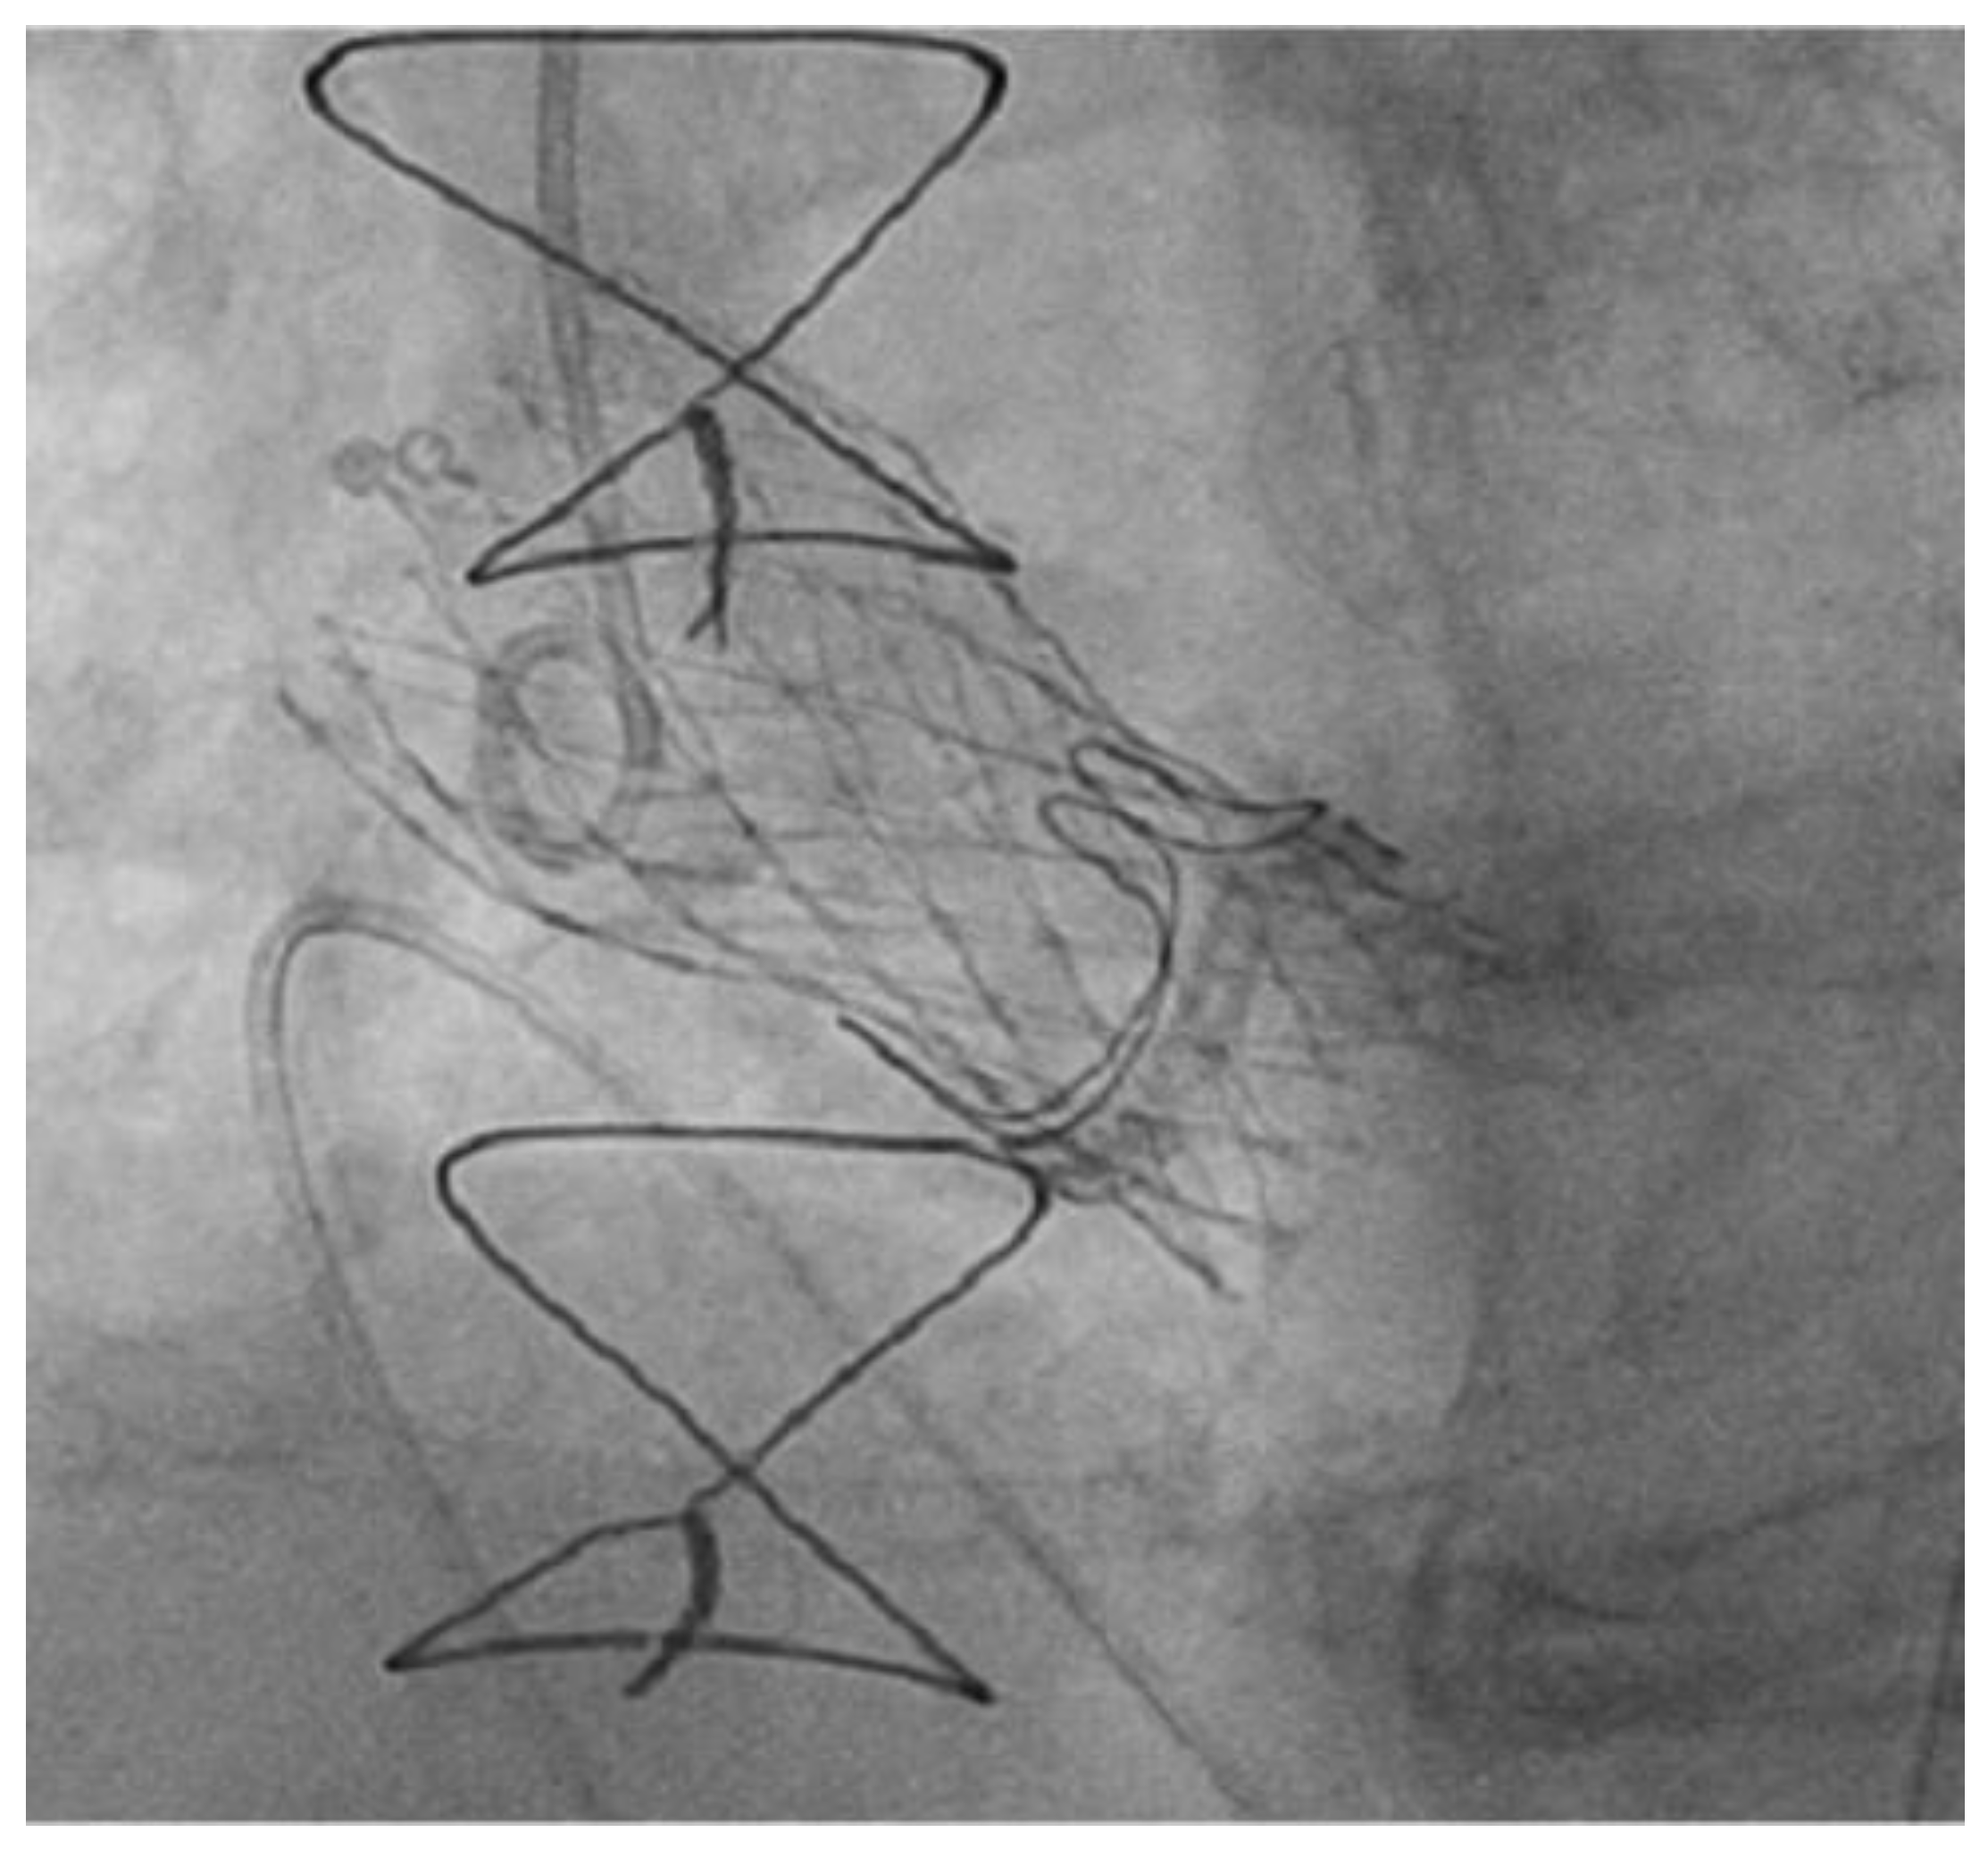

- Fede, A.; Romano, M.; Buffoli, F.; Camurri, N.; Lettieri, C. Combination of Double Chimney Technique and Prosthesis Post-Dilation after Valve-in-Valve Implantation. Case Rep. 2020, 2, 2173–2175. [Google Scholar] [CrossRef]

- Mercanti, F.; Rosseel, L.; Neylon, A.; Bagur, R.; Sinning, J.M.; Nickenig, G.; Grube, E.; Hildick-Smith, D.; Tavano, D.; Wolf, A.; et al. Chimney Stenting for Coronary Occlusion during TAVR: Insights from the Chimney Registry. JACC Cardiovasc. Interv. 2020, 13, 751–761. [Google Scholar] [CrossRef]